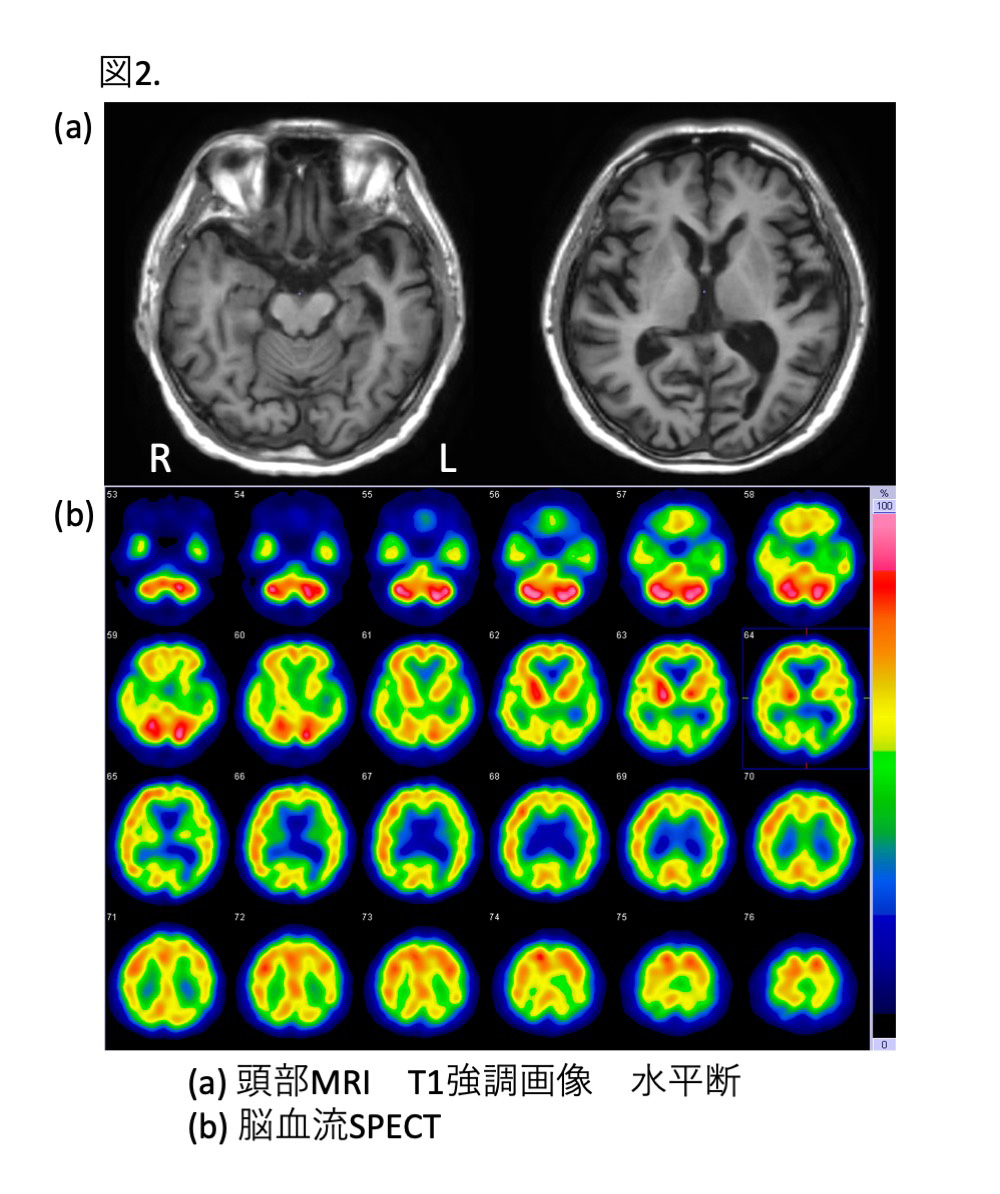

p.269掲載の図2